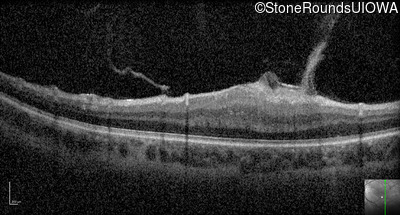

Optical Coherence Tomography - Left - 20/80

Exemplar / OCT Stack